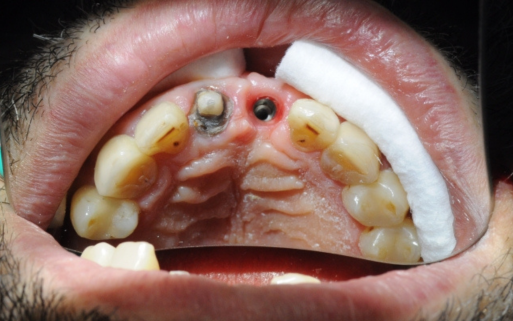

Wielu młodszych pacjentów, w wieku 25-35 lat, ignoruje problem utraty pojedynczego zęba, uważając go za mało istotny. Tymczasem nawet brak jednego zęba może prowadzić do poważnych konsekwencji, takich jak

Nieuzupełniona przestrzeń zęba powoduje stopniową utratę kości w tym miejscu, dlatego warto odtworzyć brakujący ząb implantem z koroną. Wczesna odbudowa zęba pozwala uniknąć wyższych kosztów w przyszłości, które mogą obejmować dodatkowe zabiegi, takie jak odbudowa kości czy podniesienie dna zatoki szczękowej. Nie czekaj – jeśli brakuje Ci jednego zęba, skontaktuj się z nami i przywróć estetykę oraz funkcjonalność swojego uśmiechu!

Przed i Po Naszych Klientów